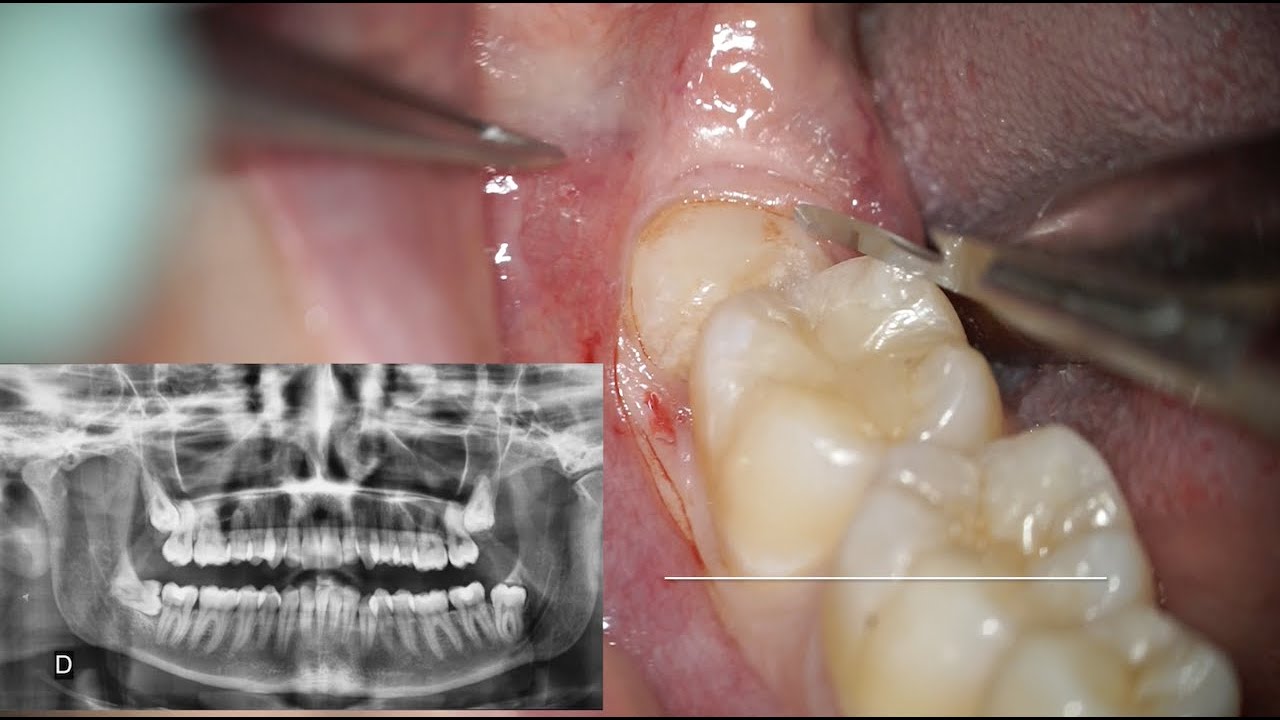

Informazioni Estrazione dente del giudizio inferiore. Lower third molar extraction

Microscope third molar extraction

Estrazione dente del giudizio: rischi, procedure e tecniche più